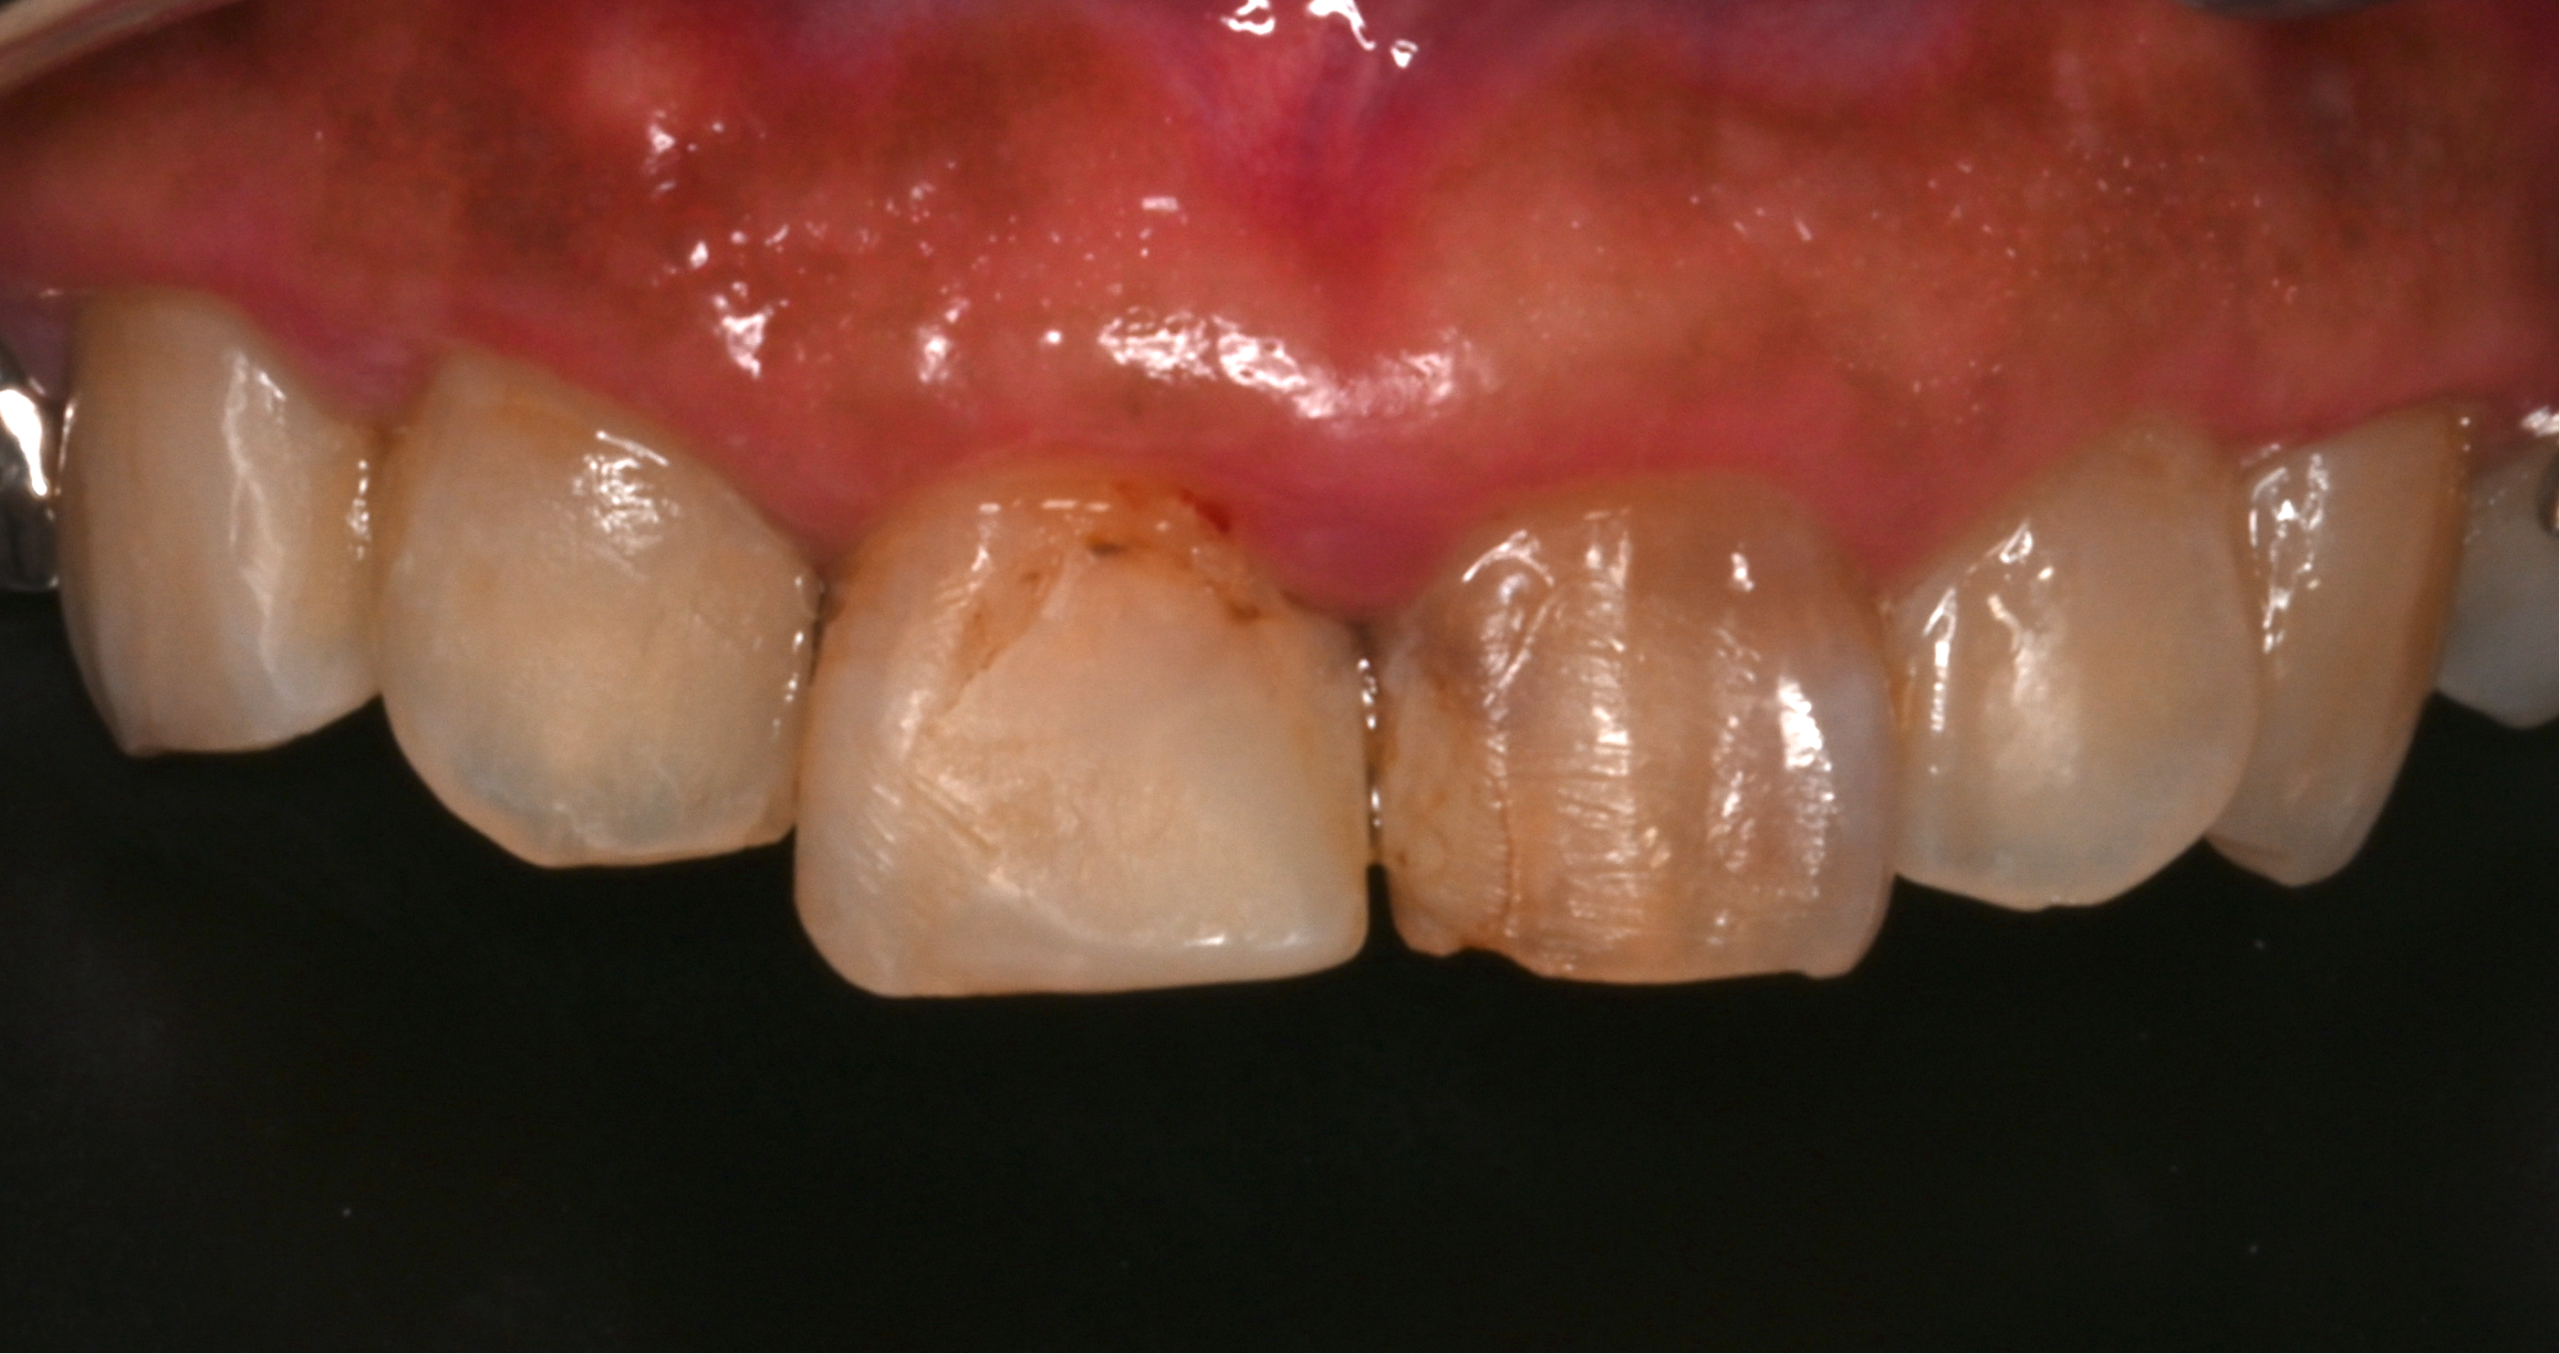

治療前

| 治療内容 | 虫歯治療、セラミックブリッジ治療 |